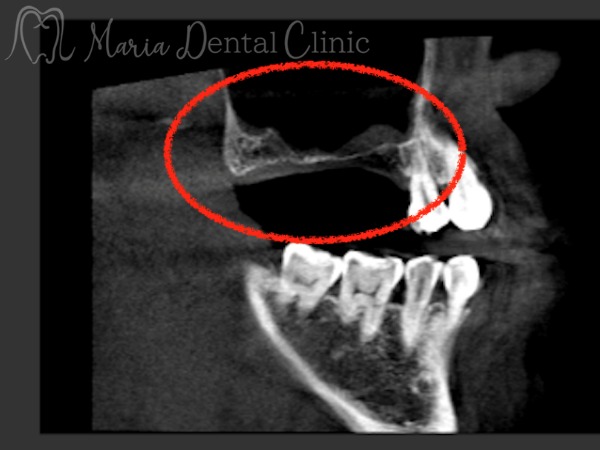

今回のように、重度の歯周病を患ってから抜歯をおこなった場合、抜歯後の歯周組織の喪失が著しくなります。特に上顎は上顎洞が近接しているため、インプラント埋入の骨量が不足することが多々見受けられます(画像赤丸○部分)。

上顎の骨量不足に対してはGBR・ソケットリフトの他に、今回のように比較的広範囲に骨が必要な症例では、サイナスリフト(上顎洞挙上術)を行うことで、インプラントを支える新たな骨を確保することができます。(外科画像1)

サイナスリフトでは、側方から上顎洞粘膜を挙上し、できた空間に人工骨を填入することで3〜6ヶ月後にインプラント埋入可能な骨が形成されます(赤二重丸◎部分)。